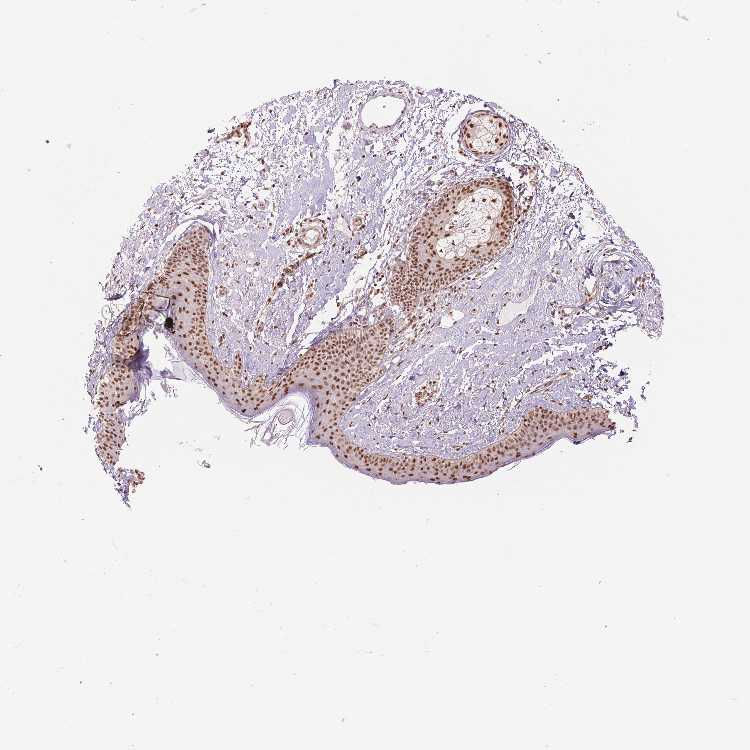

SKIN 1 - Antibody stainingi

Antibody staining in the annotated cell types in the current human tissue is reported as not detected, low, medium, or high, based on conventional immunohistochemistry profiling in selected tissues. This score is based on the combination of the staining intensity and fraction of stained cells.

Each image is clickable and will lead to virtual microscopy that enables deeper exploration of all samples and also displays staining intensity scores, fraction scores and subcellular localization as well as patient and tissue information for each sample.

Antibody HPA062997Antibody CAB014874

Langerhans HighHigh

Fibroblasts HighHigh

Keratinocytes HighHigh

Melanocytes HighHigh